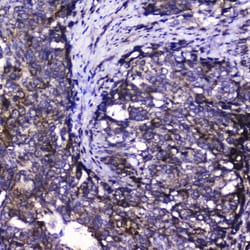

Invitrogen™ CDK6 Polyclonal Antibody

Reconstitute with 0.2 mL of distilled water to yield a concentration of 500 μg/mL. Positive Control - WB: human Hela whole cell, human Jurkat whole cell, human K562 whole cell, mouse RAW2647 whole cell. IHC: human intestinal cancer tissue, human mammary cancer tissue.

| Applications | ELISA, Immunohistochemistry (Paraffin), Western Blot |